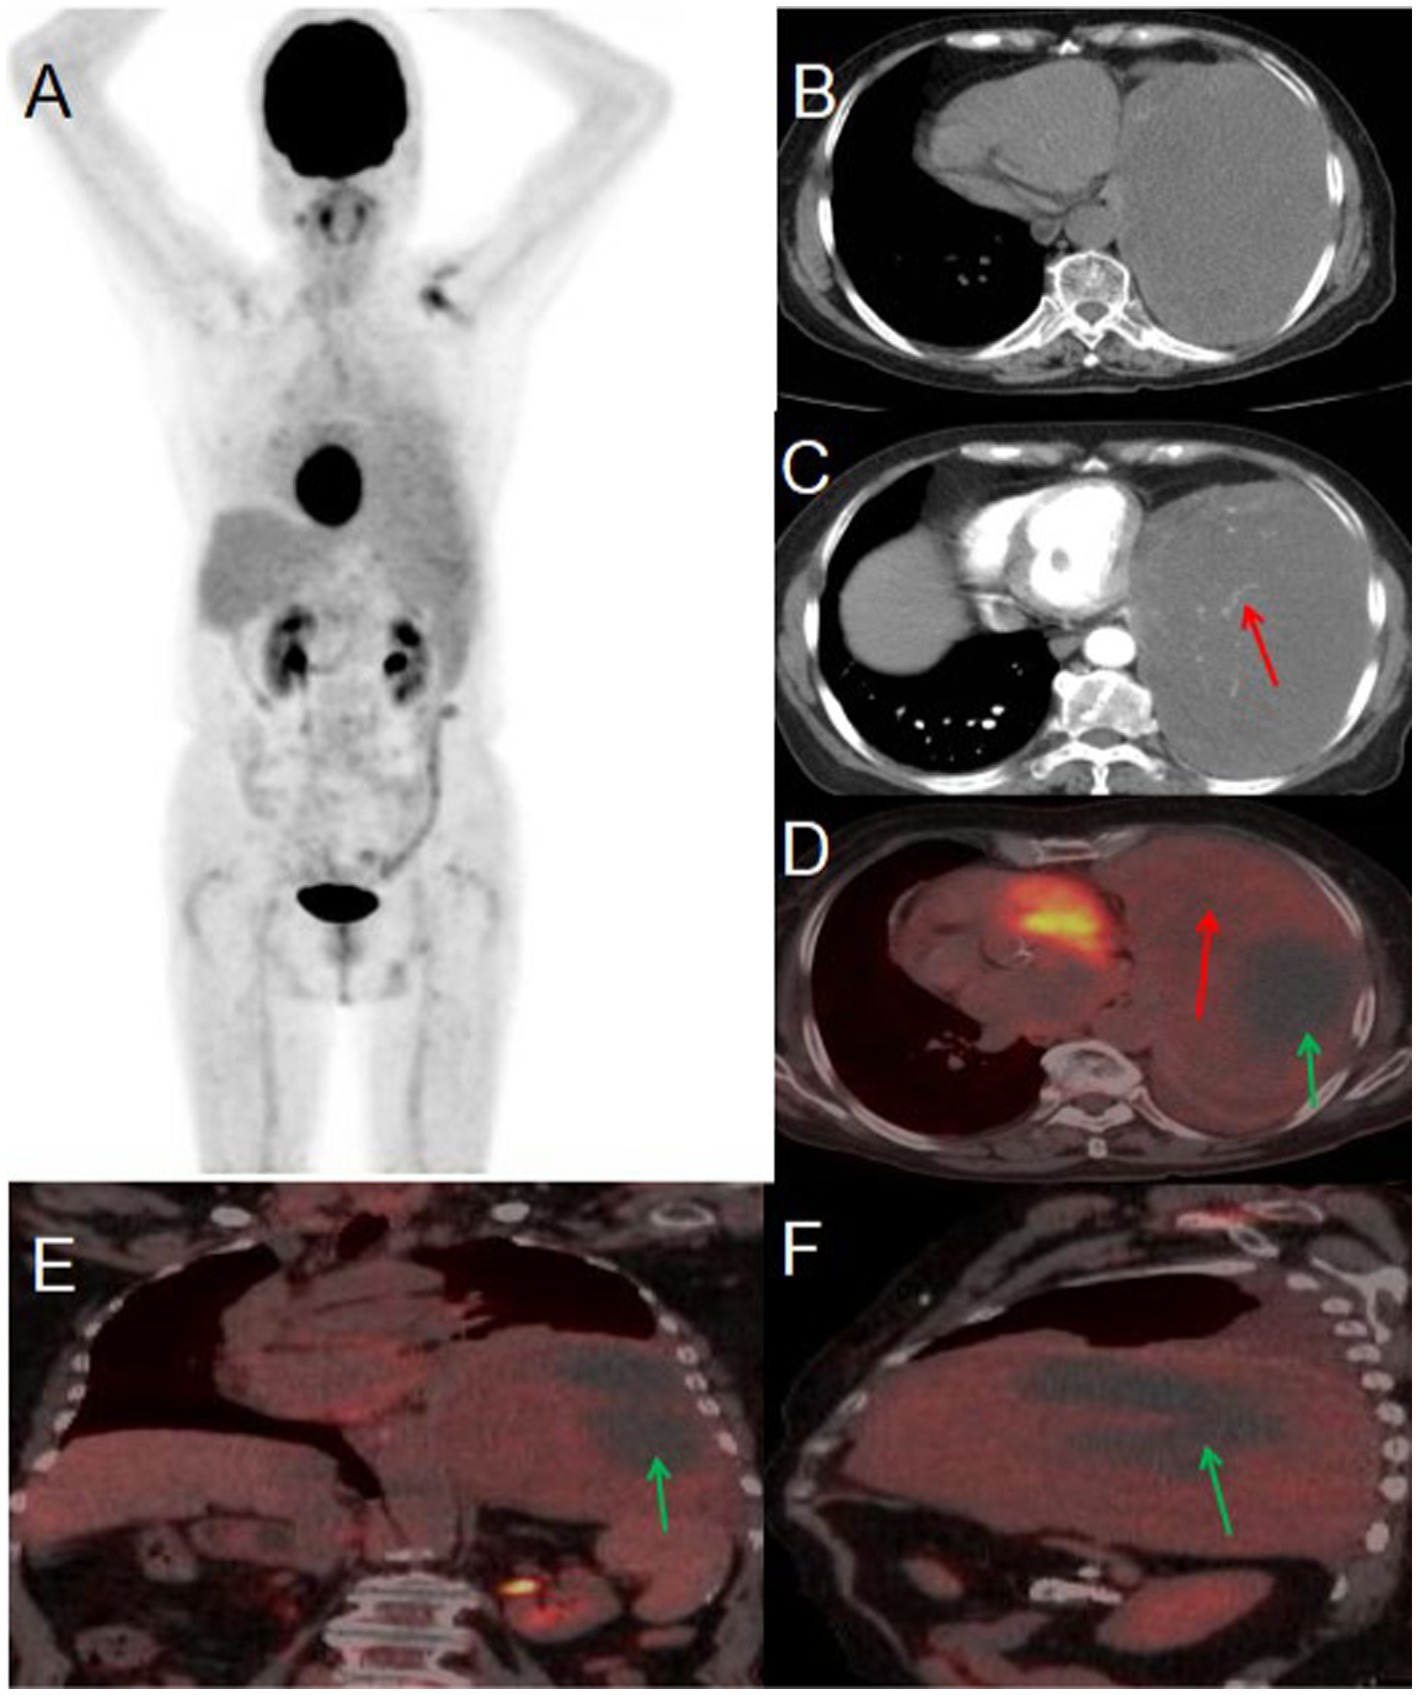

An 80-year-old woman presented to the hospital on May 22, 2024, with a one-month history of persistent cough and two days of chest pain. She had initially developed a dry cough one month prior, occasionally producing blood-streaked sputum, which she had dismissed as non-serious. Two days before admission, she began experiencing left-sided chest pain that she reported was not clearly related to breathing or coughing movements. The patient had no history of chronic disease and a history of other types of tumor. For further evaluation and management, she was referred to Jiangxi Provincial People’s Hospital. Contrast-enhanced CT imaging revealed a large, irregular soft tissue mass in the left lung demonstrating heterogeneous density with visible necrotic areas, measuring approximately 153 × 99 mm in maximum cross-sectional dimension. The contrast-enhanced scan showed heterogeneous enhancement with prominent vascular shadows and partial encapsulation of the lesion. These CT findings were strongly suggestive of a malignant pulmonary tumor. Tumor marker examination results included: AFP 2.9 (0–7 ng/mL), CEA 2.03 (0–6.5 ng/mL), ferritin 248.00 (30–400 ng/mL), CA199 9.16 (0–27 U/mL), NSE 21.90 (0–16.3 ng/mL), CF21-1 4.42 (0–3.3 ng/mL), CA125 104.00 (0–35 U/mL). PET/CT imaging demonstrated a large, heterogeneous soft tissue mass in the left lung measuring approximately 97 × 157 mm in maximal dimension, featuring areas of necrosis and poorly defined margins. The lesion exhibited mildly increased heterogeneous FDG uptake with a maximum standardized uptake value (SUVmax) of 2.3. Whole-body PET/CT showed no evidence of metastatic disease. Given the relatively low metabolic activity observed, the imaging findings were most consistent with a benign solitary fibrous tumor of the lung. After multidisciplinary tumor board review, the patient proceeded to surgical resection. Histopathological examination of the resected specimen confirmed the diagnosis of solitary fibrous tumor (see Figure 2).

Figure 2

Male, 80 years old, benign primary pulmonary solitary fibrous tumors. (A) Whole body MIP. (B) Axial, non-contrast-enhanced CT. (C) Axial, enhanced CT-arterial phase. (D) Axial fusion. (E) Coronal fusion. (F) Sagittal fusion. PET/CT imaging revealed a large, mixed-density soft tissue mass in the left lung with necrosis and indistinct boundaries, measuring approximately 97 × 157 mm at its largest dimension. The mass exhibited slightly increased heterogeneous FDG uptake, with an SUVmax of 2.3 (red arrow, D), while no FDG uptake was observed in the low-density necrotic area (green arrow, D–F). The contrast-enhanced CT scan showed an irregular, large soft tissue mass in the left lung with heterogeneous density and visible necrosis. The enhanced scan demonstrated heterogeneous enhancement with prominent vascular shadows (red arrow, C) and local encapsulation.